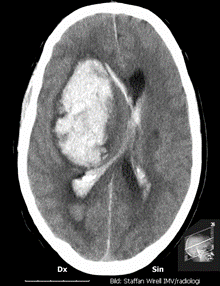

Typ av undersökning? Vad visar bilden?

På akutmottagningen tar neurologjouren emot och bestämmer sig relativt omgående för att göra en akut datortomografi av hjärnan. Under väntetiden blir Hjalmar allt mer motoriskt orolig och oklar. Narkosläkare tillkallas och man tvingas söva och intubera patienten för att kunna genomföra röntgenundersökningen. Neurologjouren meddelas röntgensvaret och tillkallar omgående neurokirurgjouren. Då hon ser patienten på akuten är han sövd men nu är höger pupill större än vänster och de drar endast ihop sig trögt och ytterst lite då man lyser i dem. Patientens puls har börjat sjunka och är nu nere på 40/min. Hon beslutar om utrymning av hematomet och Hjalmar förs omedelbart till operationssalen. Under transporten dit får han intravenöst Mannitol och hyperventileras.